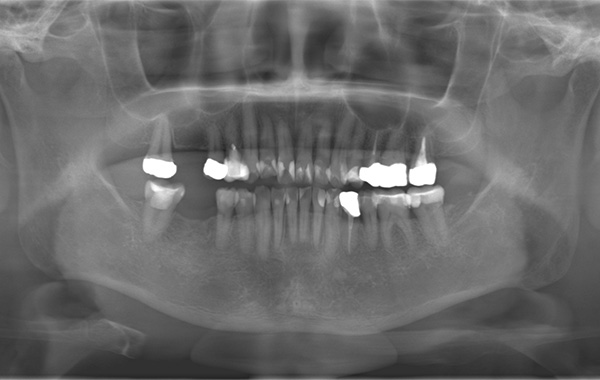

レントゲン写真(治療前)

レントゲン写真